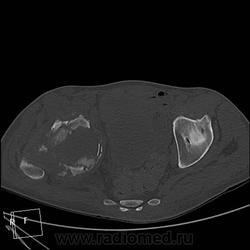

Мужчина 37 лет. Травму отрицает. Верификации нет, и неизвестно, будет ли. Думаю на остеосаркому. Характерно ли такое распространение до L3?

Лежал около месяца в другом ЛПУ, парез, отек конечности, преходящий парез другой конечности, худеет, слабость. К нам однократно в январе привозили на КТ головного мозга для исключения инсульта - исключили. Поступил вчера, в направлении "заболевание спинного мозга?", направлен на КТ грудного и поясничного отдела и таза для исключения мтс в позвоночник и перелом шейки правого бедра. В позвоночнике деструкции не нашла. Анализов пока тоже нет. Температура в норме.

ЗНАЧИТ ТАК - ТУТ ИМЕЕТ МЕСТО ПАТОЛОГИЧЕСКИЙ ПЕРЕЛОМОВЫВИХ В ОБЛАСТИ ПРОКСИМАЛЬНОГО ЭПИМЕТАФИЗА ПРАВОЙ БЕДРЕННОЙ КОСТИ !!САМ ПРОЦЕСС СКОРЕЕ ВСЕГО КАК С ОСТЕОЛИТИЧЕСКИМ ,ТАК И ОСТЕОБЛАСТИЧЕСКИМ КОМПОНЕНТОМ С ПРЕОБЛАДАНИЕМ 1-ГО.ИМЕЕТСЯ МЯГКОТКАННЫЙ КОМПОНЕНТОМ С УЧАСТКАМИ ПОНИЖЕННОЙ ПЛОТНОСТИ и обызвествлениями,разбросанными по периферии!!ПО ПЕРЕДНЕ ЛАТЕРАЛЬНОМУ КОНТУРУ ВЕРХНЕЙ ТРЕТИ ДИАФИЗА И МЕТАФИЗА БЕДРА ОПРЕДЕЛЯЕТСЯ ИГОЛЬЧАТЫЙ ПЕРИОСТИТ. В ПРОЕКЦИИ ЭПИМЕТАФИЗА ОПРЕДЕЛ-СЯ МНОЖЕСТВЕННЫЕ ФРАГМЕНТЫ РАЗНОЙ ДЕНСИМЕТРИЧЕСКОЙ ПЛОТНОСТИ/вдоль повздошных сосудов по задней и паравертебрально определяется инфильтрация восполительная или опухолевая.?местами ограниченные участки с низкой плотностью ,конгломерат увел лимфат -ких узлов ?с включениями извести в проекции крыла повздошной кости и повздшно поясничной мышцы.перелом патологич в области седалищной кости и крыши вертлужной впадины с остеолитическим компонентом ,в теле повздошной кости участок деструкци и со склеротической каймой !!

мой диагноз ходросаркома ,которая в отличие от остеосаркомы часто встречается в метаэпифизе бедренной кости+возраст 37лет тоже в пользу 1 ой.на счет перелома он патологический !!!даже если на данный момент нет шейки и головки !просто странно что только сейчас к вам направляют на потдверждение перелома .на счет вывиха даже в случае полного разрушения верхняя треть диафиза не там где нужно,смещена латерально и кзади ,на счет игольчатого периостита ,это конечно мое мнение пересмотрите 5срез в аксиальном костном режиме и 2 во фронтальном .и кстати на пятом в просвете прямой кишки определяется экзофитно растущее образование ? скорее всего это какашка извиняюсь за выражение но все же перепроверте может и то что мне кажется)))))ну и не нравится зона в проекции повздошно поясничной,повздошной и большой поясничной мышц с включениями извести и сниженной денситометрической плотностью ограниченных участков в центре .это может поменять диагноз первичного поражения мышц (саркома ) на кость вторично!предлагаю законтрастировать кишечник и сделать контрастное исследование (болюс)и посмотреть -что за природа этого участка .?

Выяснилось, что пациент болен с конца ноября 2011 года, когда с люмбоишалгией был госпитализирован в больницу. Лечился без особого успеха. Выписан. Через пару дней снова поступил в ту же больницу с фебрильной тепмературой и подозрением на пневмонию. В выписке данных о рентгенограммах позвоночника нет, гемоглобин 102, лейкоциты 3,6, СОЭ 3 мм/ч, общий анализ мокроты без особенностей. RW отрицательная. Обзорная рентгенография ОГК по выписке - норма. Родственники просили проконсультировать частного невролога, заключение: энцефалопатия смешанного генеза (токсическая+посттравматическая - последствия нескольких сотрясений головного мозга), правосторонний грубый спастический монопарез, образование спинного мозга?, рекомендовано МРТ. На МРТ не поехал.

У нас RWотрицательная, биохимия в норме, общий анализ мочи в норме; гемоглобин 86, лейкоциты 10, палочки 2, СОЭ 16 мм/ч. Температура от нормы до 37,5 С, жалобы на боли в правом тазобедренном суставе, пассивные движения крайне болезненные, активные отсутствуют. Консультация невролога у нас, заключение такое же.